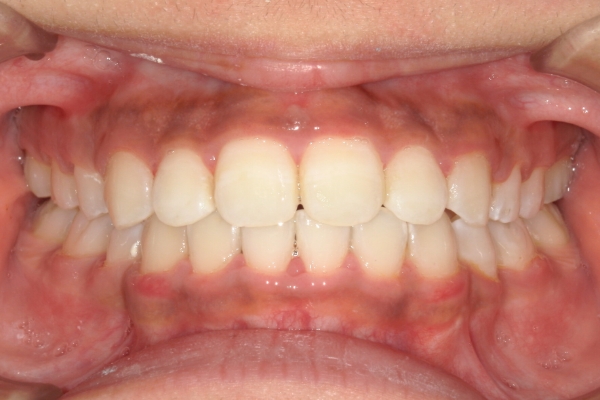

AFTER

治療後

上顎前歯が1 cm近く前方に出ており、叢生を改善しつつ前歯を大きく引っ込めるために上下顎小臼歯の抜歯が必要と診断しました。治療では奥歯の噛み合わせのズレも整え、治療後は前歯でも奥歯でも食べ物が噛みやすくなったと、患者さまに非常に満足していただけました。